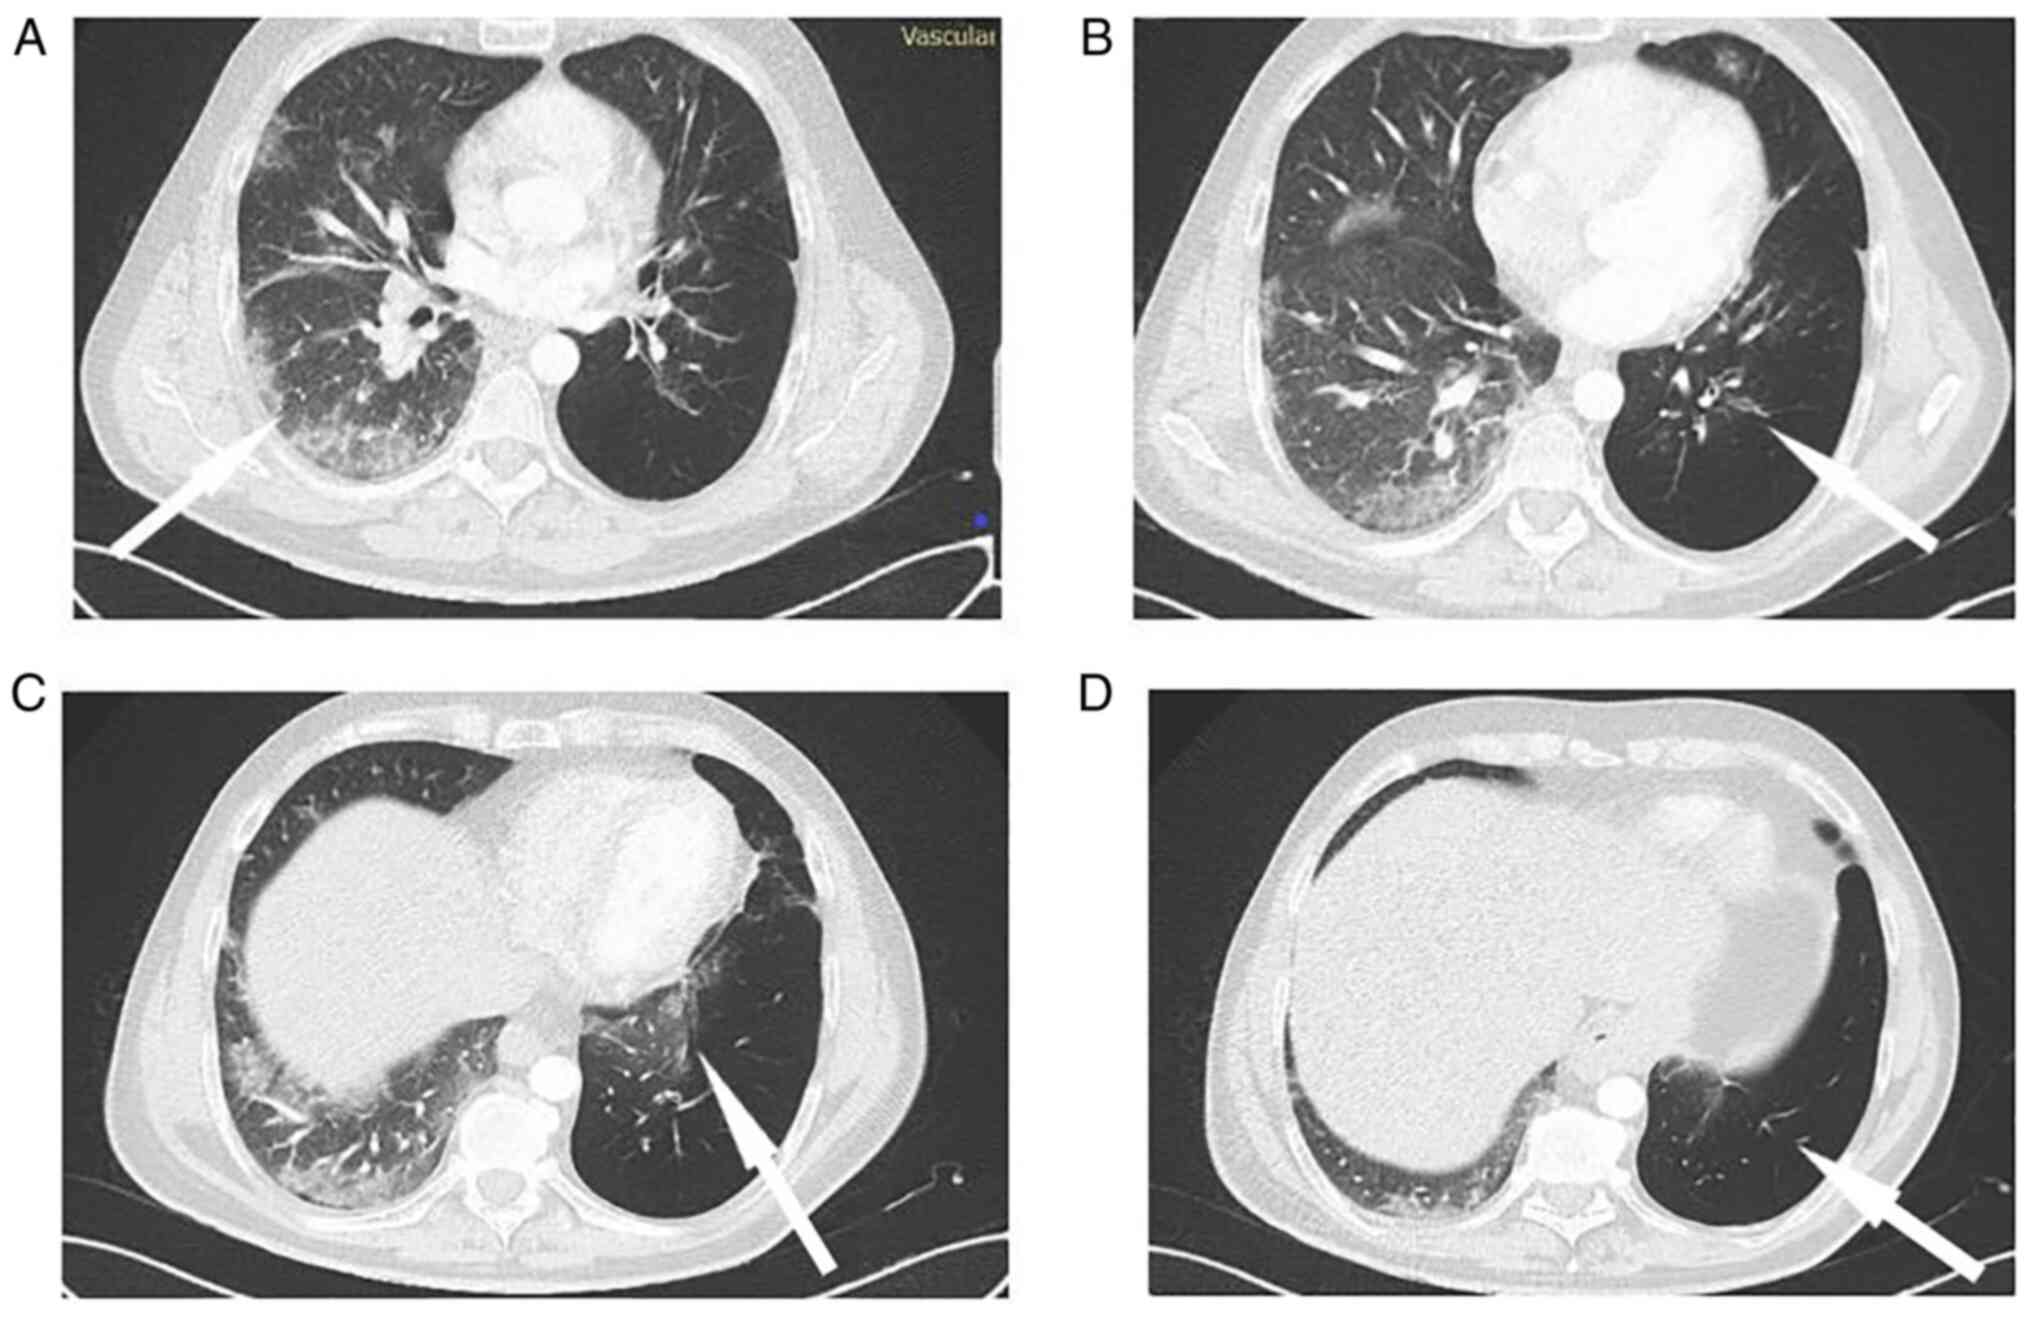

The patient was also advised to continue receiving the combination of inhaled bronchodilators during his hospitalization. He underwent a computed tomography pulmonary angiogram, which revealed no pulmonary embolism, and a high-resolution computed tomography scan of the chest, which revealed lung infiltrates in all lung fields of the right lung, as well as a hyperlucent left lung with bronchiectasis and much fewer lung infiltrates (Fig. 2). Furthermore, a sputum culture was performed that did not reveal any microorganisms, and therefore the patient did not receive any antibiotics.

Figure 2

Chest computed tomography scan. (A) Arrow indicates infiltrates in the right lung. (B) Arrow indicates bronchiectasis in the left lung. (C) Arrow indicates infiltrates in the left lung. (D) Arrow indicates hypelucency of the left lung.